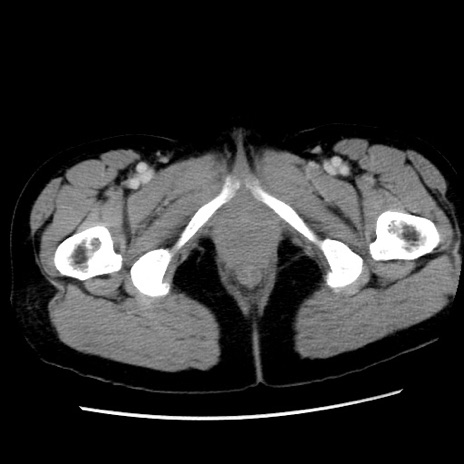

症例10(横断像)

【症例】 50歳代女性

【主訴】 腹痛

【現病歴】前日生レバーを食べた。今朝に排便あり。 昼前に突然発症の腹痛を生じ、当院救急外来を受診した。

【既往歴】 子宮筋腫にてで子宮全摘後

【身体所見】 意識清明、腹部:平坦、軟、下腹部やや左を中心に圧痛・反跳痛あり、筋性防御あり

【データ】WBC 7800、CRP 0.07